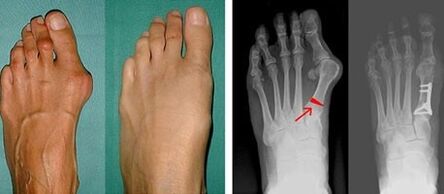

Valgus deformity of the first foot most often affects women of mature age, but it also affects men.A deformed thumb base does not look aesthetically pleasing.In this case, the person feels physical discomfort, and in an advanced stage - pain.Big foot deviation is the result of uneven body load on the foot.Such changes have adverse effects on the feet and other fingers.

If the visual examination and x-rays do not give any results, then the patient is referred to panography to determine possible flat feet.This method involves taking a foot print, based on shoes or insoles with orthopedic properties made for the patient.The patient is then prescribed pedometry.This method uses computer analysis to determine the pressure of a person's weight on the feet.Advanced diagnostic results are the basis for choosing a treatment method for first and second foot curvature.

At the first stage of identifying valgus big toe and little toe, the doctor conducts a visual examination.In this way, it determines the level of pathological development.To identify detailed changes in the joints, x-rays and plans are prescribed.